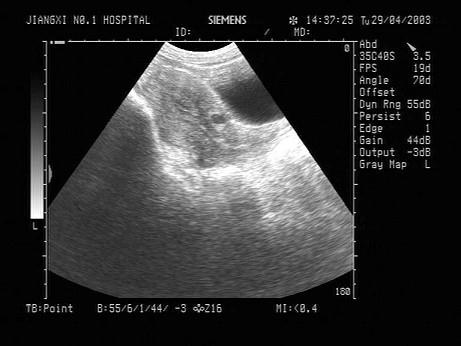

问题 女性,32岁,因反复外阴瘙痒、白带异味就诊。超声检查如图,应诊断为?(?)

选项 A.子宫内膜癌 B.宫颈囊肿 C.子宫肌瘤 D.宫腔残留 E.宫颈炎

答案 B